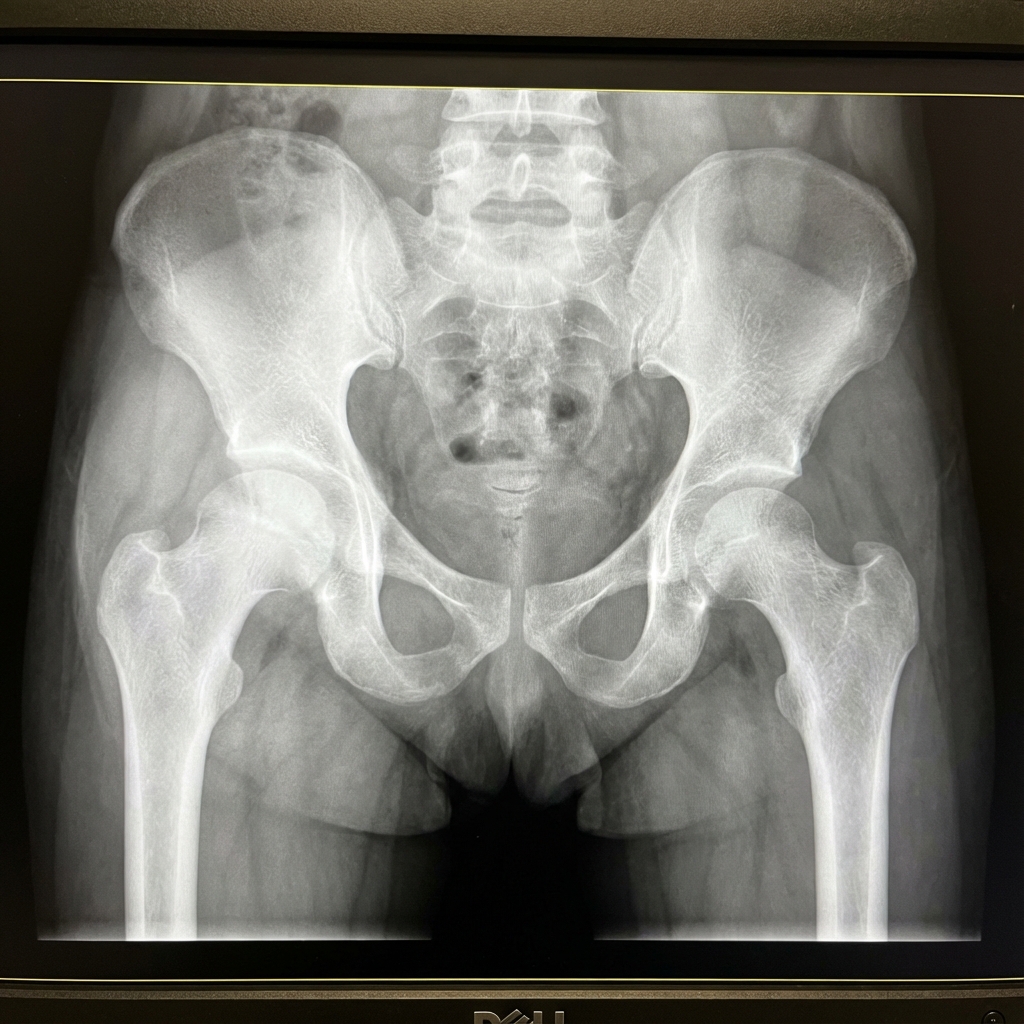

AP pelvis radiograph of a 4-year-old child with transient synovitis of the right hip. There is subtle widening of the joint space compared to the left, suggesting effusion. The femoral head and acetabulum appear normal with no bony abnormalities. Shenton's line is intact bilaterally. There is no evidence of Perthes disease changes. Ultrasound confirmation of effusion is recommended.

Image source: Open Access medical literature (NIH/PubMed Central) • CC-BY License